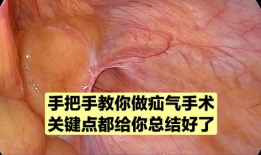

疝气手术视频,从术前准备到术后恢复

你有没有想过,当你在网上搜索“疝气手术视频”时,会出现什么样的画面呢?今天,就让我带你一起揭开这个神秘的面纱,看看那些让人既好奇...